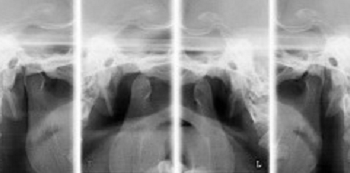

顎関節(TMJ)↑レントゲン写真